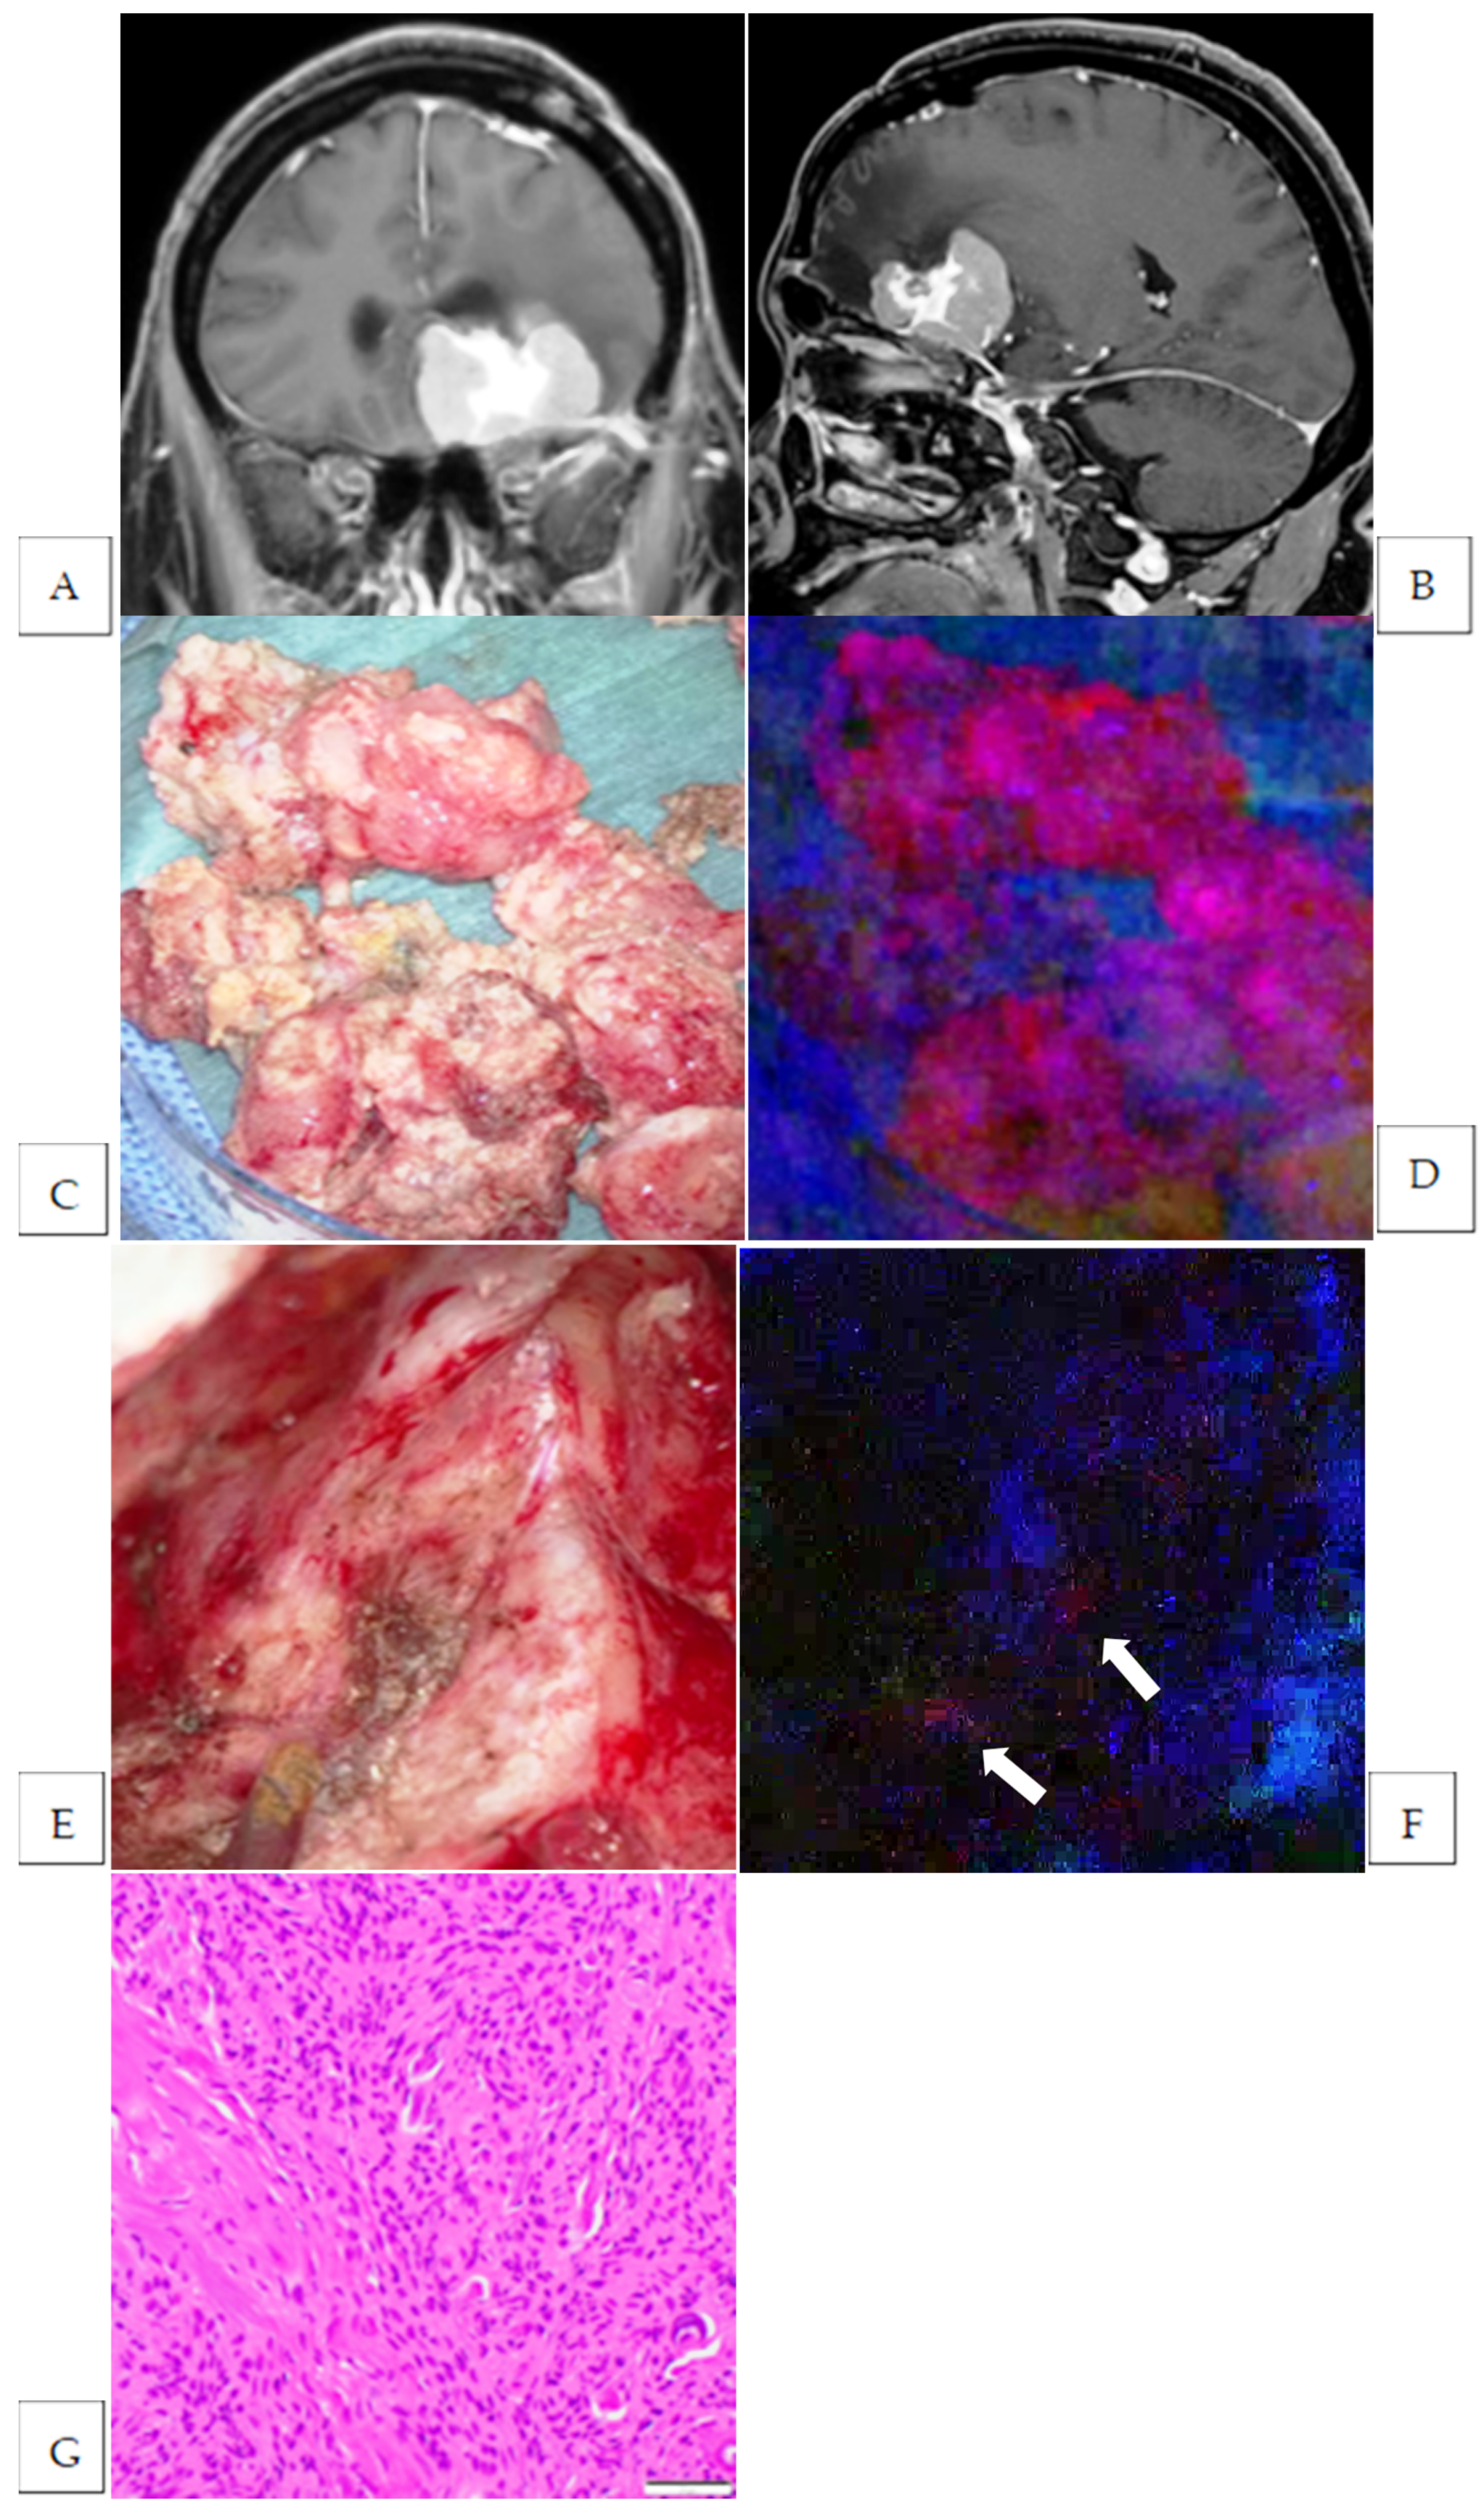

| 6 | trigone of the lateral ventricle | meningothelial | Strong | yes | yes | brain | 1 | yes |

| 7 | middle fossa | transitional | Strong | yes | yes | brain | 1 | no |

| 8 | convexity | meningothelial | Strong | no | no | |||

| 9 | convexity | meningothelial | Strong | yes | yes | brain | 1 | no |

| 12 | convexity | transitional | Vague | yes | yes | brain | 1 | no |

| 13 | sphenoid ridge | transitional | Strong | yes | yes | brain | 2 | yes |